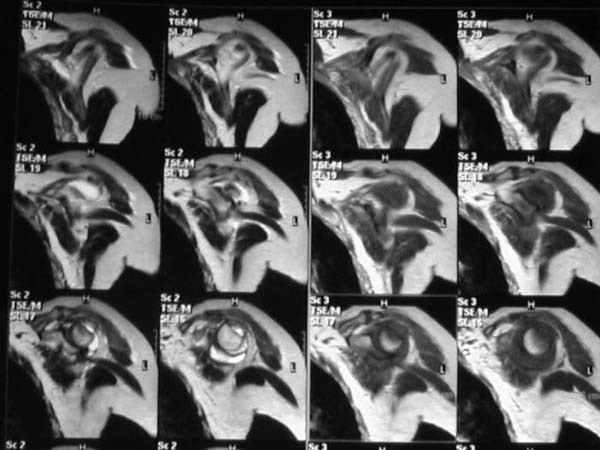

Уважаемые коллеги!Женщина, 60 лет. 3 недели назад упала с упором на отведенную левую руку. Почувствовала боль в левом плечевом суставе. За помощью не обращалась. 2 недели "мази и припарки". Затем - рентгенограмма (r1 и r2), жалобы на боли,ограничение движений...

Активное отведение 80 гр., при пальпации - головка плечевой кости безболезненно вправляется и тут же самостоятельно вывихивается. Наложена косыночная иммобилизация, рентгенография (r3) и МРТ.В нашем диагностическом центре МРТ исследование плечевого сустава выполнено впервые, опыта у нас маловато :(.Вопросы: уточнение диагноза? какие исследования провести? тактика лечения?

МРТ1МРТ2МРТ3МРТ4

Из того, что видно на недостаточно качественно отсканированных МРТ - нижний подвывих плеча и синовиит. Непонятный очаг по заднему контуру головки плеча (то ли артефакт, то ли косой срез, проходящий между головкой и большим бугорком). Сухожилия вращательной манжетки выглядят целыми. Неправильная форма нижней части labrum glenoidale - разрыв ?

И еще одно пожелание - МРТ костно-суставной системы ОБЯЗАТЕЛЬНО нужно проводить с использованием сканов с подавлением сигнала от жировой ткани (SPIR - на Филипсах, у Вас, как я вижу - Филипс; FATSAT - на других томографах, либо STIR - есть на любых аппаратах). Только так можно увидеть отек мягких тканей и костного мозга на фоне жировой ткани.

Плоскости при сканировании плеча обязательно должно быть 3

1. Ортогональная поперечная (аксиальная)

2. Косая корональная (параллельно длинной оси диафиза)

2. Косая сагиттальная (так же параллельно диафизу плеча)

Как Вам известно, в некоторых случаях вывихи плеча сопровождаются разрывом ротаторной манжетки, отрывному перелому большого бугорка что приводит к потере наружной ротации и отведения плеча. На представленных рентгенограммах перелом не виден.

МРТ должен показать разрыв манжетки, но признаться я не большой эксперт по чтению МРТ сканов, хотя затемнение, отек мягких тканей по задней поверхности плеча видны Обычные рентгенограммы демонстрируют остеолизис в области большого бугорка.